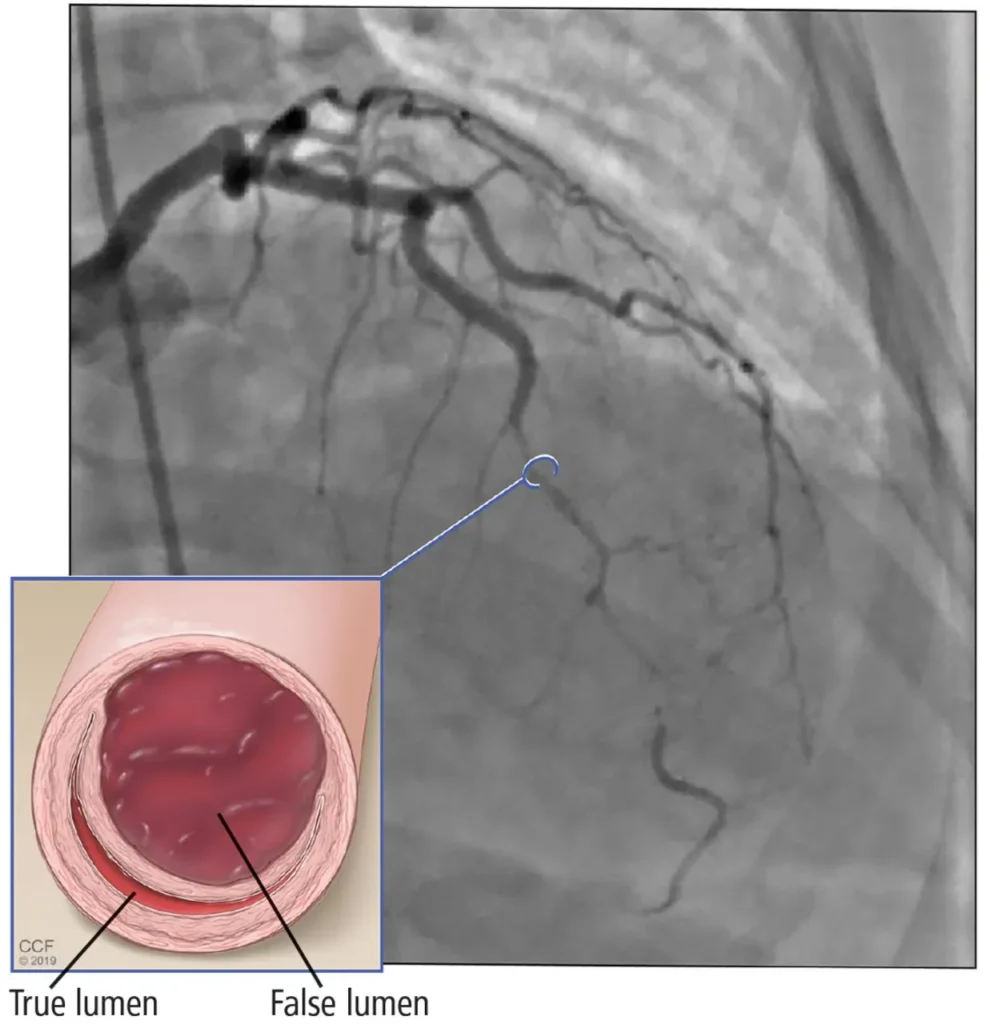

Spontaneous coronary artery dissection (SCAD) happens when there’s a sudden tear in the wall of a coronary artery. The tear causes blood to get trapped and swell inward which blocks or slows blood to the heart. This lack of blood flow can cause chest pain or a heart attack. And people who experience SCAD once are at high risk of having another tear.

- Angiogram imaging